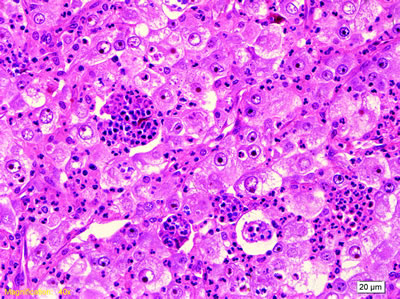

新型腫瘤的形態(tài)非常特殊,由單一的胞漿豐富的上皮樣細(xì)胞組成,胞漿嗜酸性或透明,胞膜明顯;泡狀腫瘤細(xì)胞核大、呈圓形或卵圓形、染色質(zhì)開(kāi)放,具有巨大的嗜酸性核仁;腫瘤中可見(jiàn)大量的嗜中性粒細(xì)胞浸潤(rùn),并有許多微膿腫形成。

炎癥性單形性未分化肉瘤的特殊形態(tài)